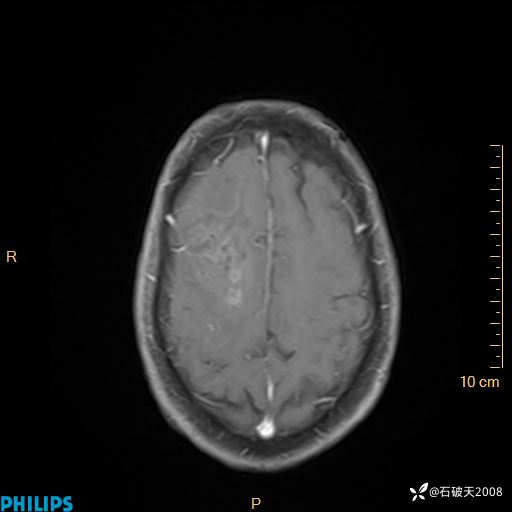

2024.2.21MR

增强轴位